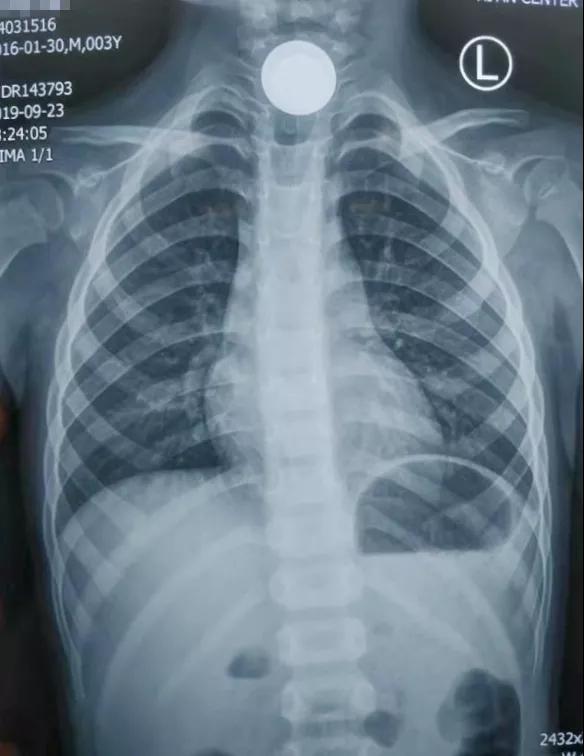

耳鼻喉科值班的主治医师王占江闻讯赶紧把孩子带进检查室,一问才知道,原来宝宝拿硬币玩,不小心将一枚一块钱硬币咽下去卡嗓子里了。孩子难受指着嗓子不停哭泣,痛苦的都说不清话了,家长心急如焚,经过详细的专科检查,王医生赶紧让孩子去拍了片子,出乎意料的是——宝宝食道里竟然卡顿了两枚硬币,一枚一元硬币一枚一角硬币!

通过急诊绿色通道,孩子顺利办好了入院手续,王医生给孩子完善急诊手术相关检查,联系手术室及麻醉科人员,禁食时间足够后安排急诊全麻手术。在手术医师、麻醉医师、手术护士紧张有序的配合下,终于将紧紧卡顿在孩子食道的一大一小两枚硬币顺利取出,孩子终于转危为安了,妈妈悬着的心也终于放下了。